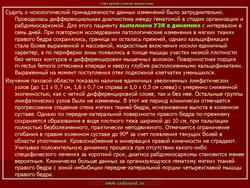

Оссифицирующий миозит

Оссифицирующий миозит